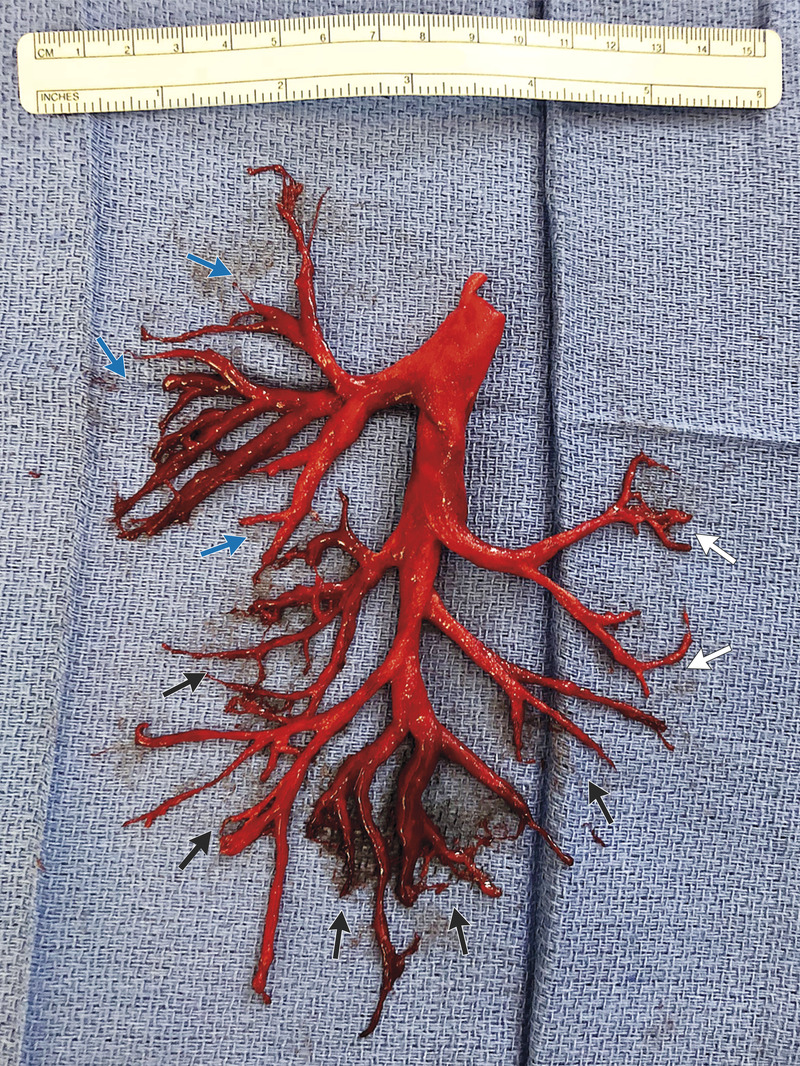

▼美國加州一名36歲的男子因為慢性心臟衰竭住院,他還經常咳血、呼吸困難。醫生想了很多辦法為他治療,但效果都不好。一次他劇烈咳嗽時,直接咳出一大片完整的右肺支氣管樹狀血塊。短短一週之後,他就離開了世界。